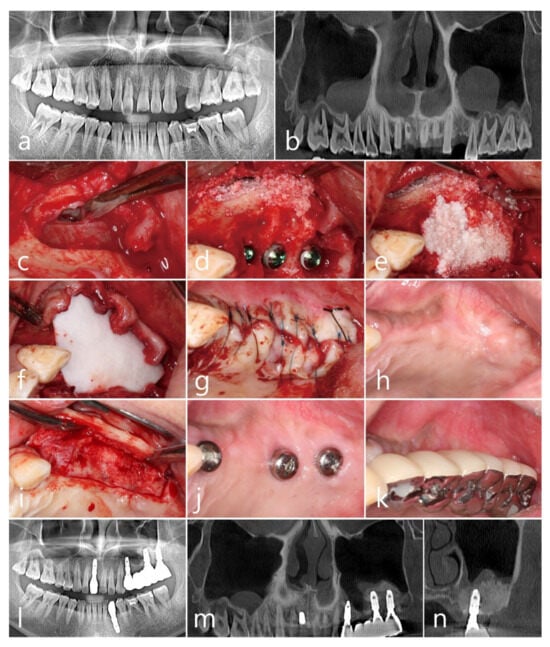

2.2. Case 2